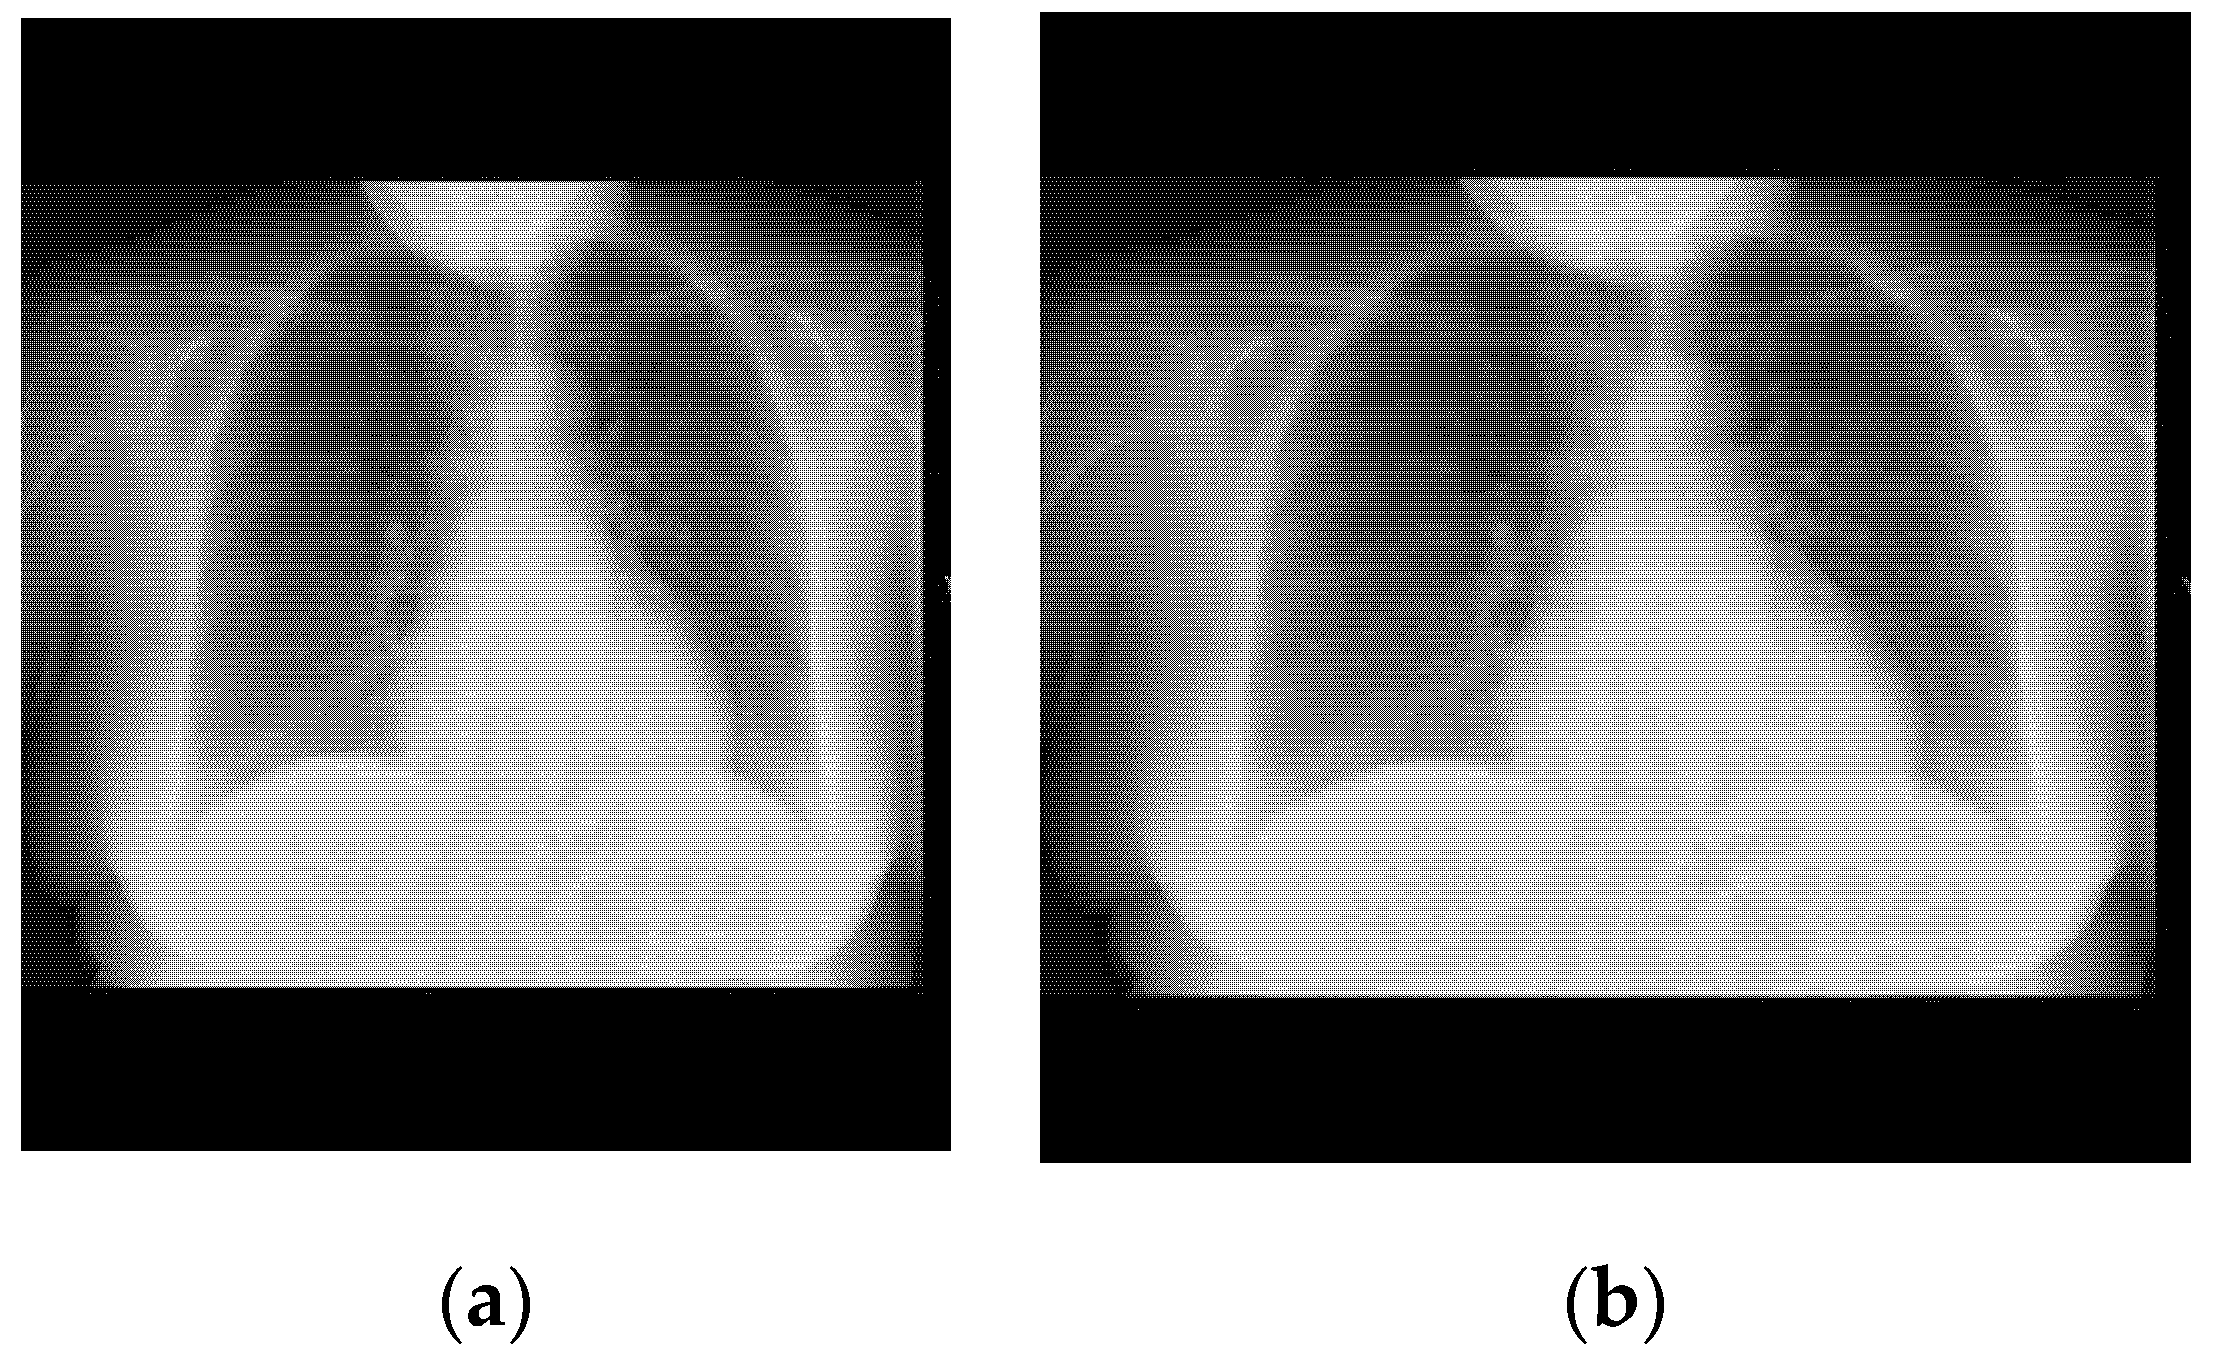

3.1. Pneumonia Dataset

3.2. COVID-19 Dataset